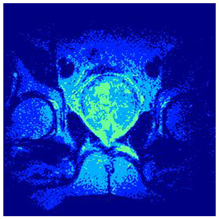

| Image | nt = 3 | nt = 4 | nt = 5 | nt = 8 |

|---|---|---|---|---|

| 1 | ![]() | ![]() | ![]() | ![]() |

| 2 | ![]() | ![]() | ![]() | ![]() |

| 3 | ![]() | ![]() | ![]() | ![]() |

| 4 | ![]() | ![]() | ![]() | ![]() |

| 5 | ![]() | ![]() | ![]() | ![]() |

| 6 | ![]() | ![]() | ![]() | ![]() |

| 7 | ![]() | ![]() | ![]() | ![]() |

| 8 | ![]() | ![]() | ![]() | ![]() |

| 9 | ![]() | ![]() | ![]() | ![]() |

| 10 | ![]() | ![]() | ![]() | ![]() |

| 11 | ![]() | ![]() | ![]() | ![]() |